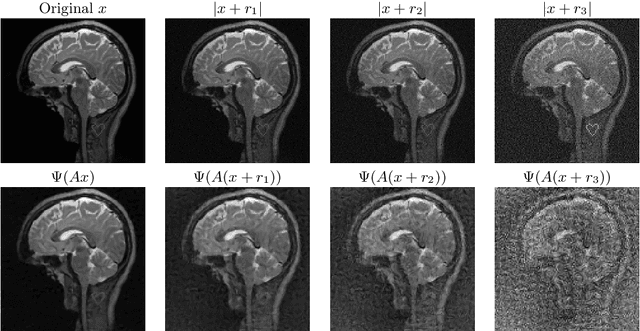

Abstract:There is overwhelming empirical evidence that Deep Learning (DL) leads to unstable methods in applications ranging from image classification and computer vision to voice recognition and automated diagnosis in medicine. Recently, a similar instability phenomenon has been discovered when DL is used to solve certain problems in computational science, namely, inverse problems in imaging. In this paper we present a comprehensive mathematical analysis explaining the many facets of the instability phenomenon in DL for inverse problems. Our main results not only explain why this phenomenon occurs, they also shed light as to why finding a cure for instabilities is so difficult in practice. Additionally, these theorems show that instabilities are typically not rare events - rather, they can occur even when the measurements are subject to completely random noise - and consequently how easy it can be to destablise certain trained neural networks. We also examine the delicate balance between reconstruction performance and stability, and in particular, how DL methods may outperform state-of-the-art sparse regularization methods, but at the cost of instability. Finally, we demonstrate a counterintuitive phenomenon: training a neural network may generically not yield an optimal reconstruction method for an inverse problem.

Abstract:Deep learning, due to its unprecedented success in tasks such as image classification, has emerged as a new tool in image reconstruction with potential to change the field. In this paper we demonstrate a crucial phenomenon: deep learning typically yields unstablemethods for image reconstruction. The instabilities usually occur in several forms: (1) tiny, almost undetectable perturbations, both in the image and sampling domain, may result in severe artefacts in the reconstruction, (2) a small structural change, for example a tumour, may not be captured in the reconstructed image and (3) (a counterintuitive type of instability) more samples may yield poorer performance. Our new stability test with algorithms and easy to use software detects the instability phenomena. The test is aimed at researchers to test their networks for instabilities and for government agencies, such as the Food and Drug Administration (FDA), to secure safe use of deep learning methods.